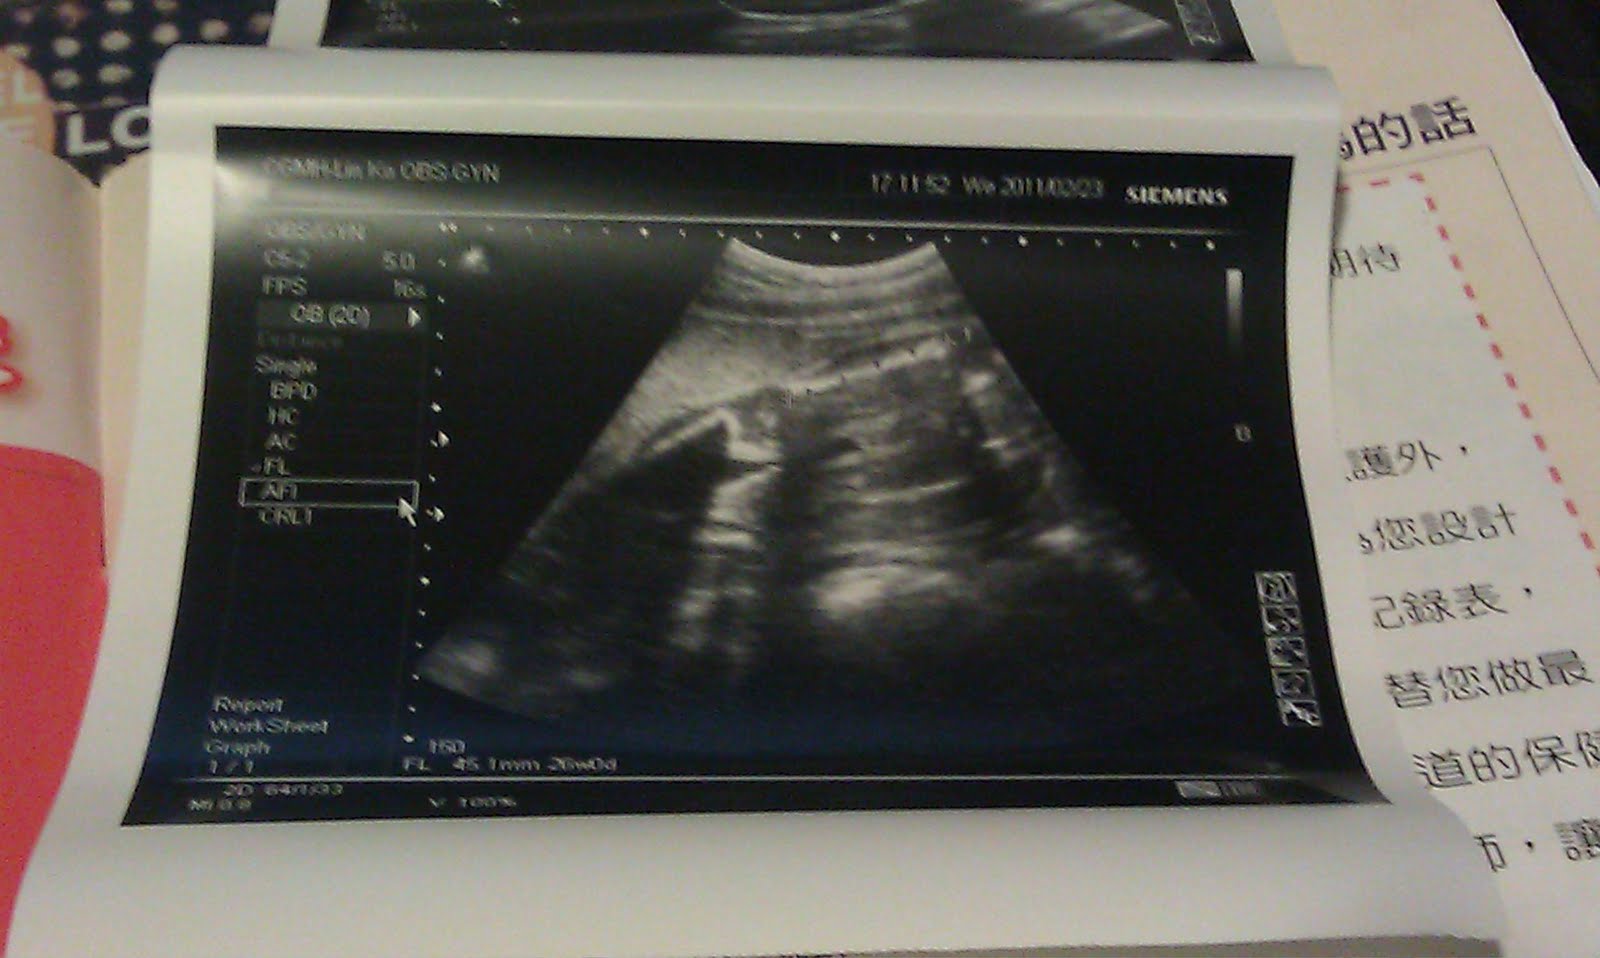

醫師是很好心的每次都會替Schumi照超音波看一下Schumi心臟,頭圍,四肢 還有體重等等

只是...我每次都看不太懂超音波的畫面..(可能我太沒有想像力了吧??) 但頭和心臟我看得出來

(這張好像是胃?!)